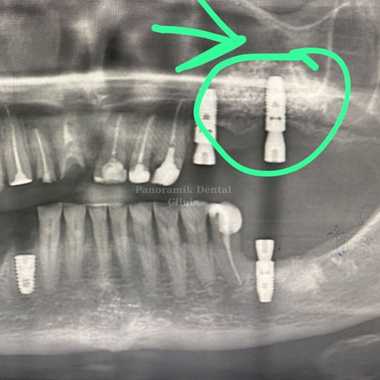

Image-1: Sinus lifting